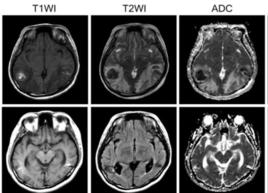

譫妄綜合徵的診斷根據起病急驟、意識障礙以及其它認知障礙症狀的晝輕夜重等特點,一般診斷不難。伴有軀體疾病、顱腦外傷以及有酒精和藥物依賴史者,有助診斷。當明確譫妄綜合徵後,應即弄清其基本病因。對急性精神分裂症與躁狂症患者伴有錯亂狀態時,可從病史與精神檢查,加以鑑別。如有疑問時,可作EEG檢查。譫妄狀態常伴有瀰漫性慢波,並與認知障礙的嚴重度相平行,可資鑑別。

精神檢查、EEG檢查以鑑別急性精神分裂症與躁狂症。